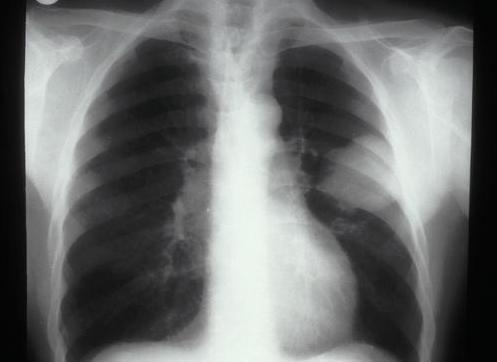

肺癌复发该怎么预防 需要注意什么?

对于肺癌康复期患者来说,最怕面临的问题就是肺癌的复发,据统计,肺癌一期的复发率为34%,肺癌二期的复发率为55%,肺癌三期的复发率为74%,所以,如何避免肺癌的复发成了肺癌患者最关注的问题,解决肺癌的复发是当前迫切需要解决的一个重大难题。

肺癌是有治愈的可能的,但是因为肺部的构造组织是比较复杂的,所以癌细胞会有被激发的可能,在治愈肺癌的时候,如果后期没用好好地护理,是会出现复发的问题的,为了防止肺癌复发,需要进行预防。下面为大家具体介绍肺癌复发的预防。